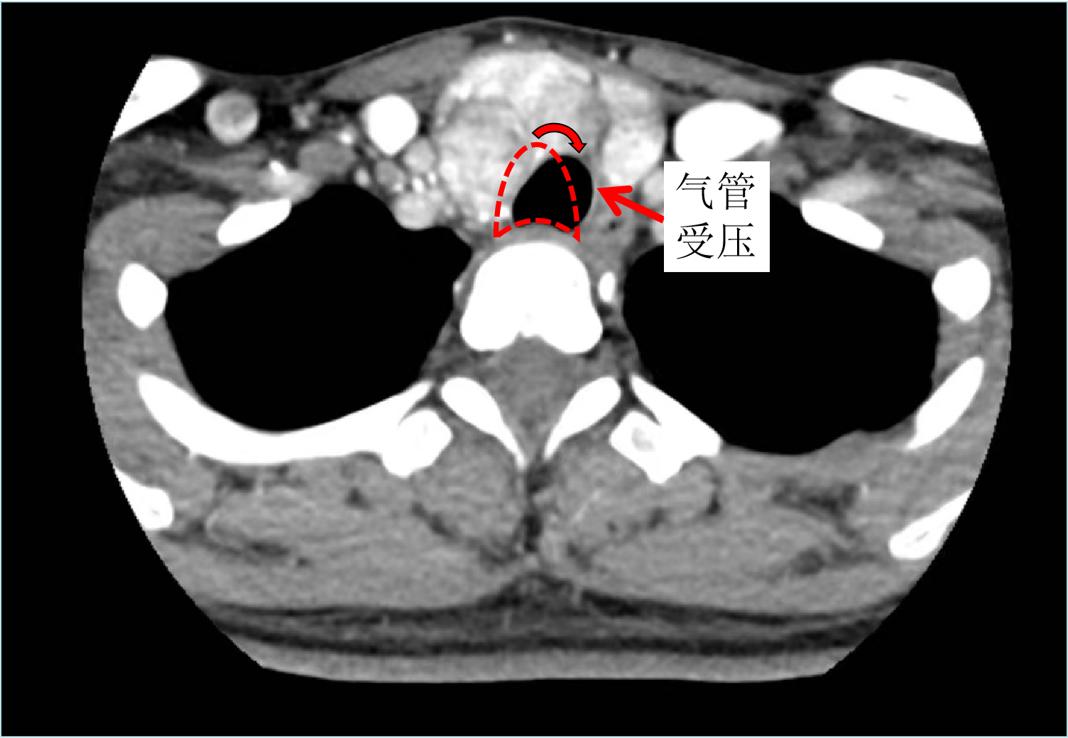

颈部巨大甲状腺结节压迫气管,使气管偏移